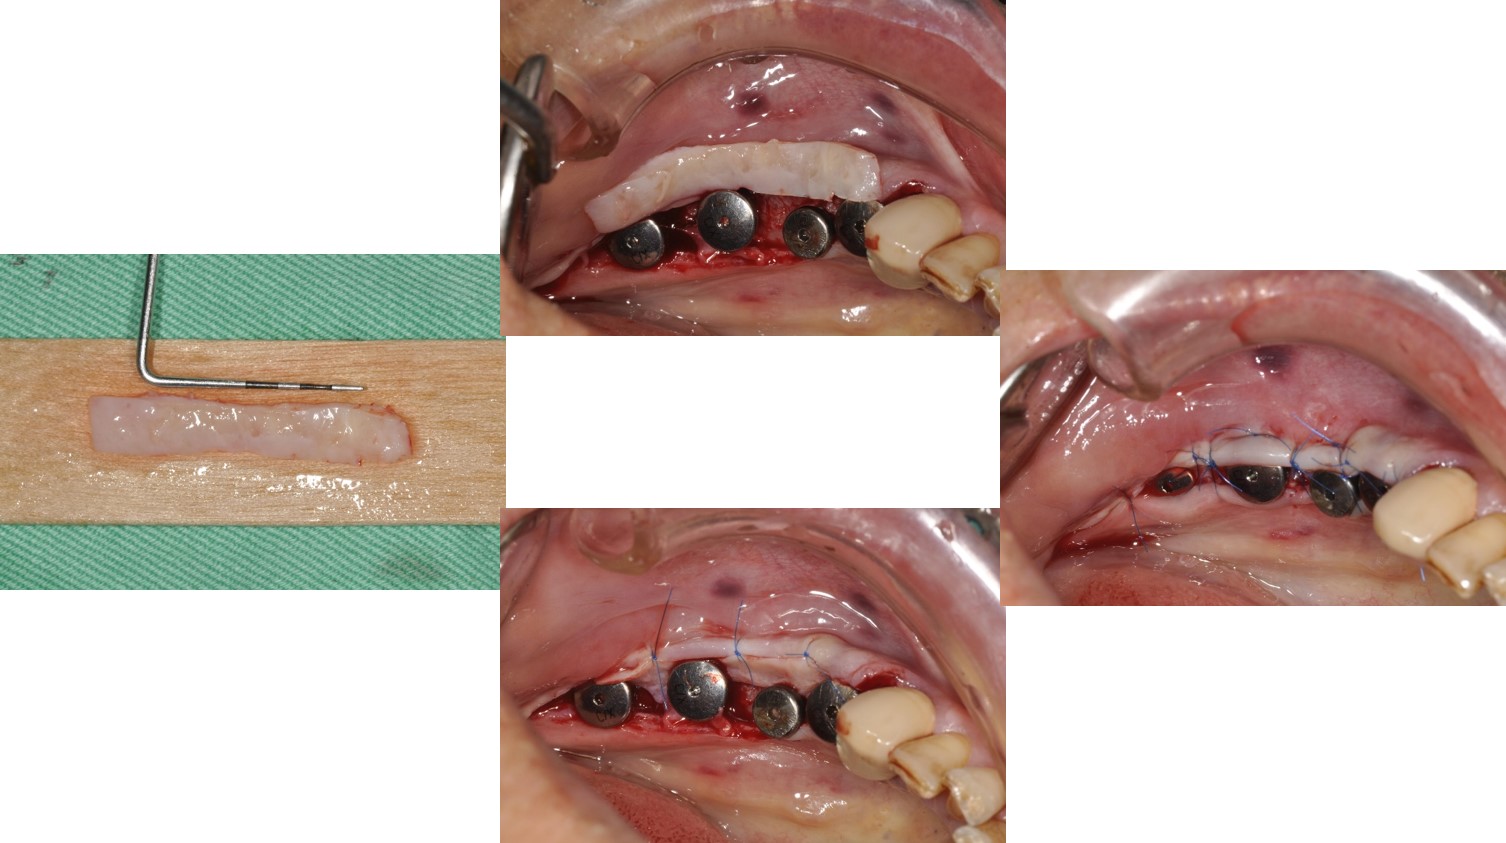

▼檢查及分析完成後,醫生就開始了植體植入與補骨手術

▼植體二階手術與補皮手術(果然照片比現場看的震撼,好在家人有打麻醉,換作是我可能光看就暈倒了吧!)

植體植入與補骨手術:#34-37

植體二階手術與補皮手術:#34-37

植體印模:#34-37

臨時假牙塑形:#34-37